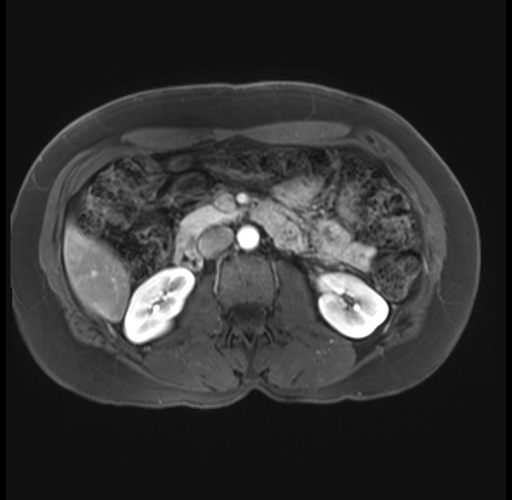

Imaging Analysis

Look through the patient's CT scan to identify any areas of concern for the necessary procedure.

Based on your CT findings, which issue(s) are present and would give reason for "planned slowing down moment(s)" in this case?

Considering a standard distal pancreatectomy procedure, what step(s) of the operation would you do differently in this case?